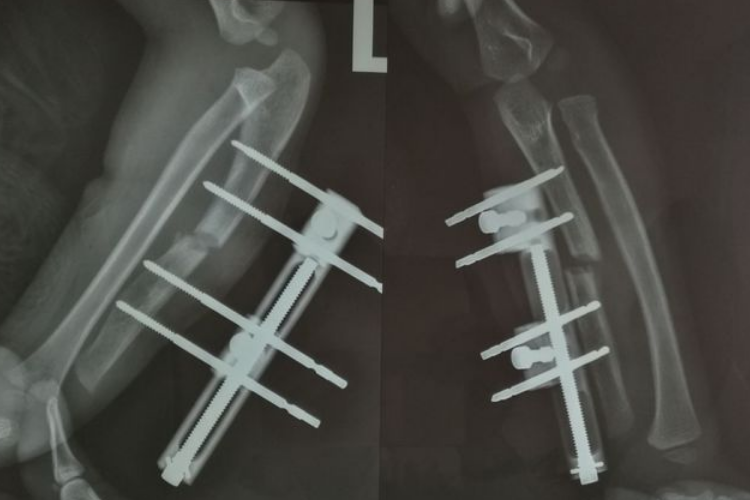

骨痂是骨延长愈合过程中新形成的连接骨折两端的骨组织,骨延长骨痂生长过程中先形成纤维骨痂再形成骨性骨痂。

在骨延长术后两周左右,由于早期大量的纤维细胞、成骨细胞等增殖活动,分泌出大量基质、成纤维细胞和成骨细胞,形成纤维骨痂,可包围并固定骨两端。

纤维骨痂形成后,成骨细胞活跃,分泌出均质透明的类骨基质,继之形成类骨组织,而后钙质在类骨基质间不断沉积形成骨组织,此时骨痂称为骨性骨痂。